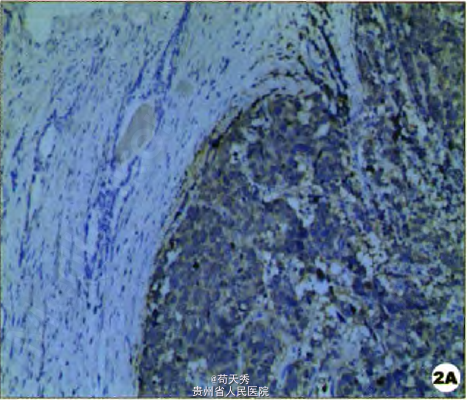

入院查体:一般情况尚可,生命体征平稳; 专科查体:双肾区无叩击痛、输尿管,走行区无压痛、膀胱区无压痛,双侧阴囊空虚;前列腺指诊:前列腺大小约I度、质地偏硬、表面尚平滑、未触及结节。 前列腺特异抗原(PSA)0.04 ng/ml;彩超检查示膀胱右后壁有一实性低回声团块(4.3 cm×2.0 Cnl),边界欠清晰,形态不规则,与膀胱壁及前列腺分界不清,彩色多普勒血流显像(CDFI):肿物内未探及明显彩色血流信号。盆腔cT:膀胱内可见不规则团块状软组织密度影,凸向膀胱腔内生长,肿瘤横截面最大4.7cm×4.0 cm,边缘可见不规则致密影,盆腔内未见肿大淋巴结。膀胱镜检查:膀胱右侧壁来源膀胱颈部尿道内口7点处可见大小约3.0 cm肿物,因肿瘤出血余膀胱壁及双侧输尿管口视不清。肿瘤表面多处取活检,病理检查提示:膀胱移行细胞癌Ⅲ级。胸部CT及腹部CT未见转移性病变、无明显。肾积水。全身骨显像:未见典型骨转移性病变图像。 术后病理报告:膀胱神经内分泌癌Ⅲ级(G3),侵犯浆膜层,可见血管内瘤栓,前列腺萎缩并可见肿瘤侵犯,双侧输尿管残端及尿道残端未见肿瘤浸润。免疫组化结果:CK20(2+)、CK7(一),前列腺特异性抗原(PSA)(一),Ki-67>50%、NSE(3+)、Syn(3+)。